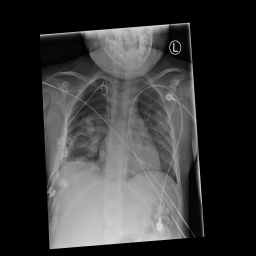

这次比赛的主要任务是从胸部X光图片中判断图片是否含有气胸,如果含有的话分割出气胸。

这次比赛所采用的数据集为胸部X光图片,训练集数目为10675张,第一个阶段测试集数据有1372张。